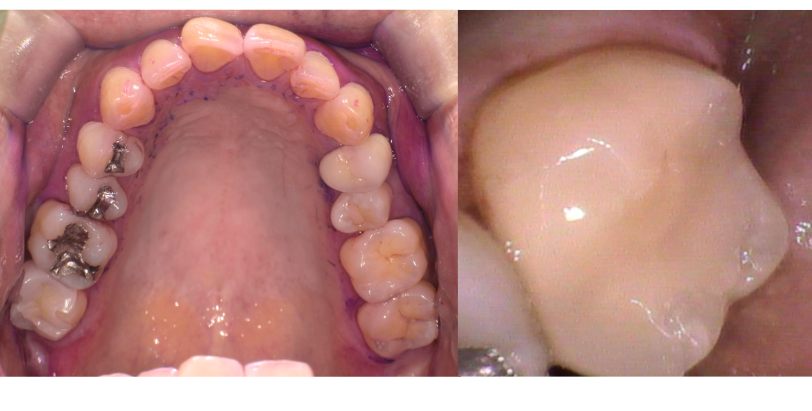

2025/04/22 セレック

OS1457様

通院時年齢 41歳

性別 女性

通院目的 虫歯が気になる

診断 ①右上4う蝕

②左上67う蝕

③左下67う蝕

処置内容 (または主訴) ①セレックインレー

②右上6セレックインレー

右上7CR

③セレックインレー

通院期間 ①~③ 3回(2か月)

費用

①セレックインレー 77,000円

82,500円

③セレックインレー 286,000円

リスク・副作用

研磨や調整が難しく定期的なメンテナンスが必要になることがある、自由診療となるため費用が高額となる

ジルコニアに比べ天然歯に近い分、破折のリスクがある

かみ合わせの変化により適宜調整を必要とする

知覚過敏の出現の可能性がある